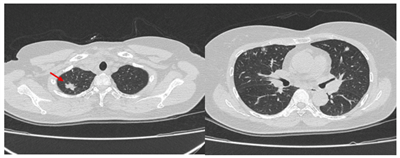

Đa ung thư nguyên phát được định nghĩa là sự xuất hiện nhiều khối u ác tính nguyên phát, khác nhau về mô bệnh học, trên cùng một bệnh nhân. Nhờ sự phát triển của các kỹ thuật chẩn đoán hình ảnh và...